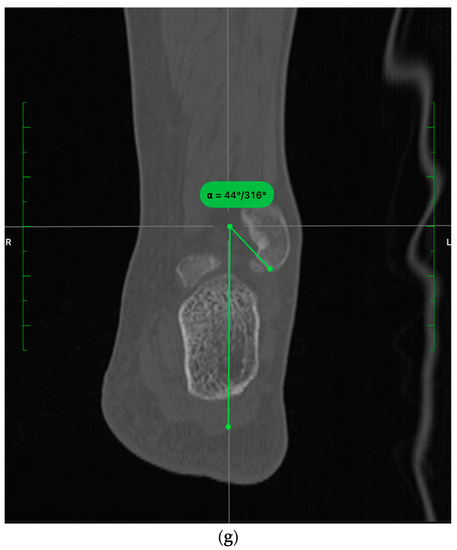

- In the sagittal plane, the lateral malleolus cartilage was fixed as anteriorly as the anterolateral tibial plafond cartilage (restoring the sagittal translation) (Figure 3)